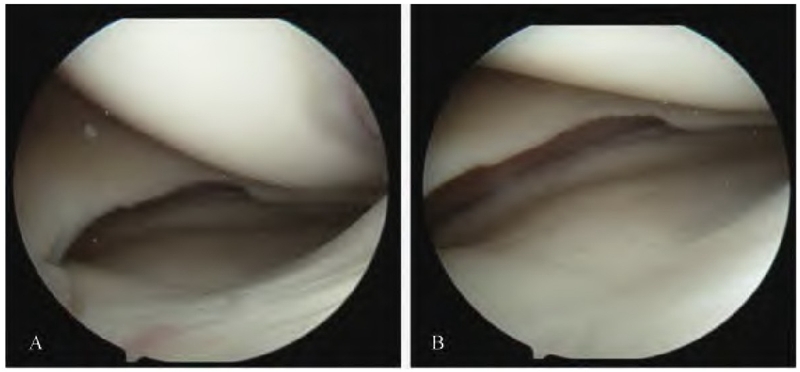

于膝关节前侧常规关节镜入路探查,清理关节内增生炎性滑膜组织,见内侧间室间隙明显增宽,内侧平台塌陷,内侧间室软骨面基本正常(图2)。探查见外侧间室间隙及软骨面基本正常,左膝前后交叉韧带及内外侧半月板未见明显损伤。

图2 关节镜检情况